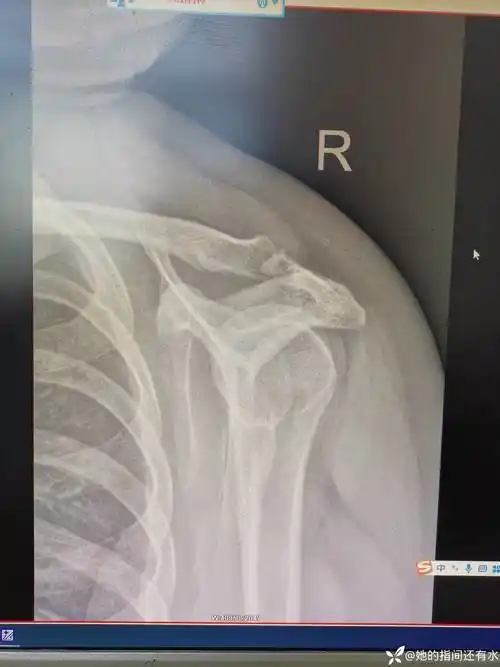

肩痛要及时就诊--陈旧性肩关节脱位病例